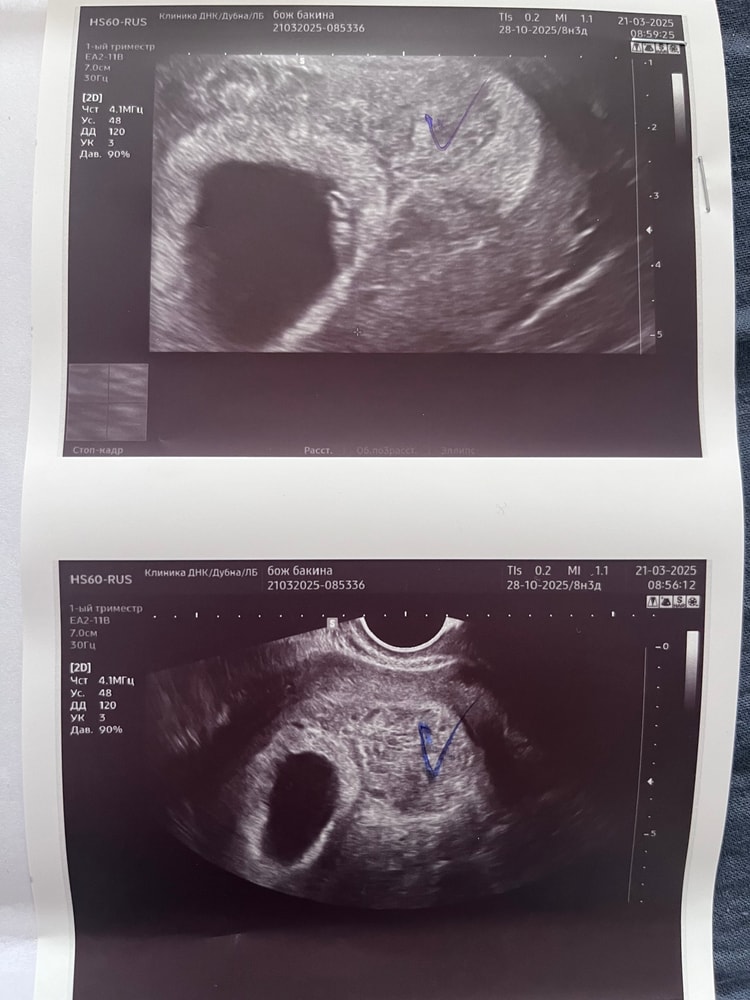

Пузырный занос?

Сегодня было узи, наконец услышали сердцебиение, 6 недель и 1 день. На прошлом узи врачу не очень понравилась динамика роста эмбриона и не слышали сердцебиения, но сегодня все нашли, эмбрион растет, я очень рада. Вместе с этим меня очень напугали. Врачу не понравился участок ткани, сказала что подозревает частичный пузырный занос. Конечно залезла в интернет, вся обревелась. Завтра поеду сдавать кровь на ХГЧ, через пару дней к врачу. Как теперь сложно в этой неопределенности. Каждый раз на узи что-то подозревают: то внематочную, то отставание в развитии, слава богу все не подтвердилось, надеюсь и ПЗ не подтвердится..:(

По узи ПЗ нельзя с точностью поставить, и даже на глаз по виду ткани невозможно определить. Только гистология. А если смотреть по узи, то надо с доплером проверять кровотоки в этом образовании.

Пузырный занос очень редко видно на узи. После гистологии у меня было подозрение на простой пузырный занос. Отправили к онкологу на консультацию, где я и задала эту кучу вопросов, которые у меня появились. Но тут совсем на мое узи не похоже. Он у меня похож был на ежика. И не было эмбриона нормального, на последнем узи он вообще исчез. Осталось пустое плодное яйцо и все.